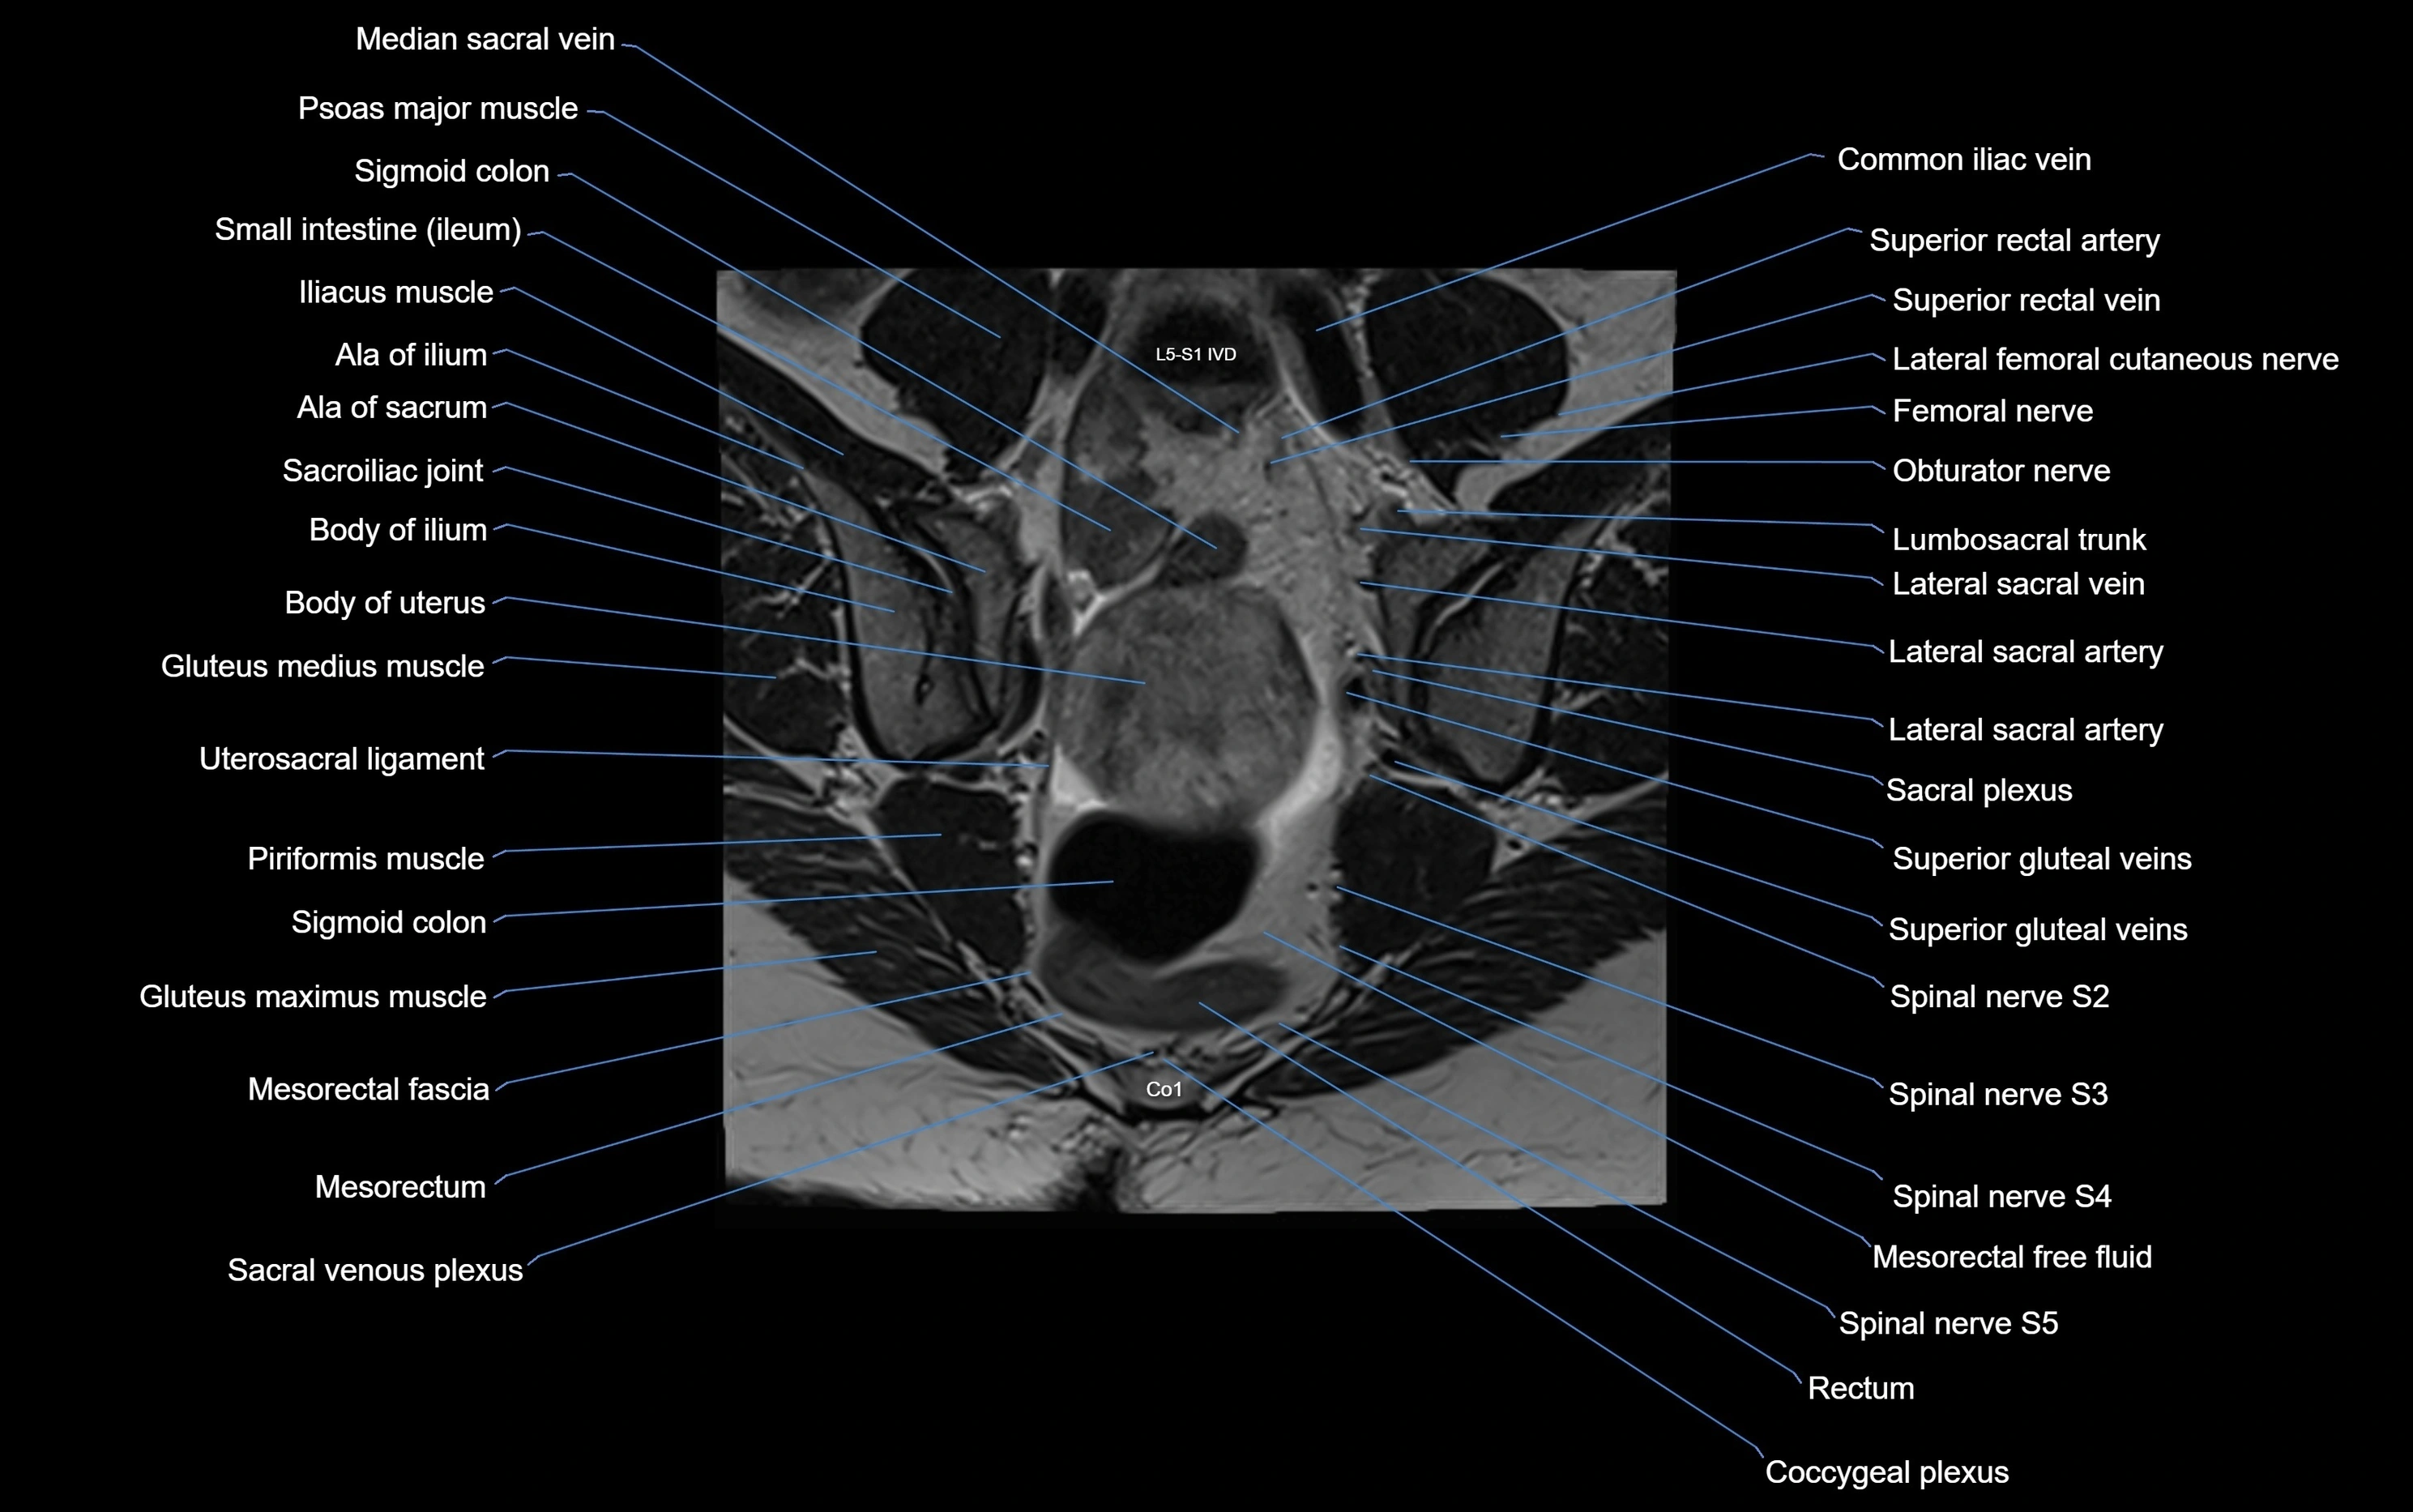

MRI image

image